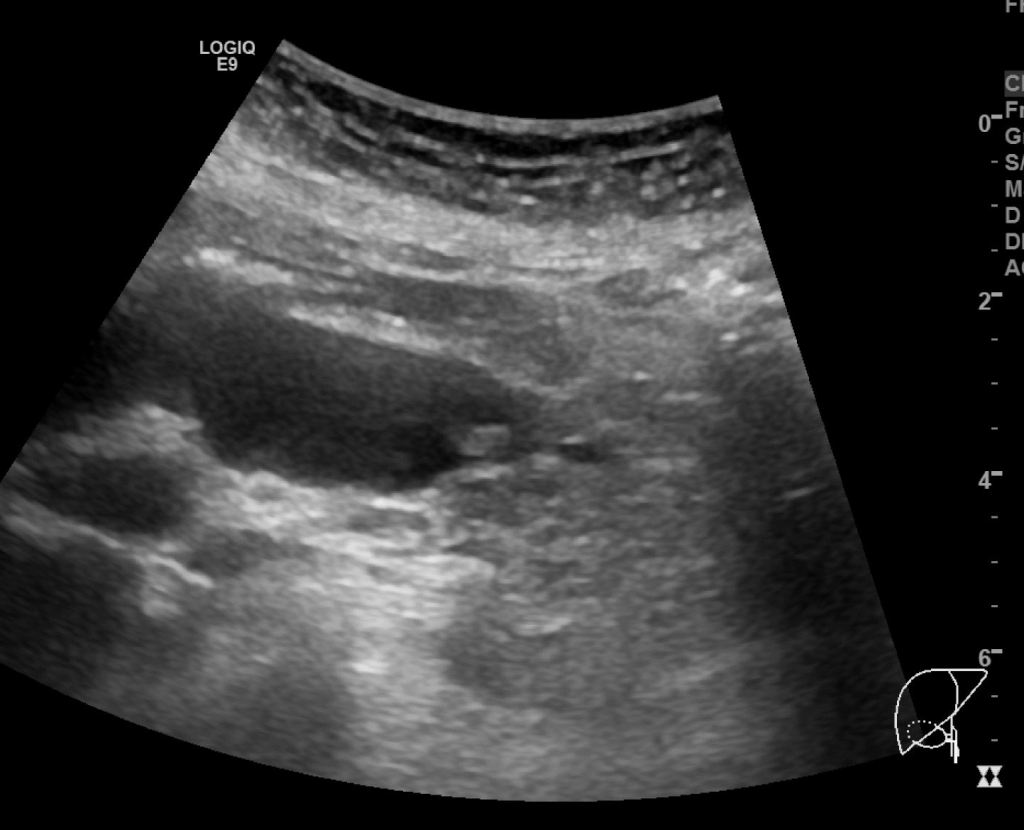

총수담관의 아래쪽 끝부위를 종단면스캔한 영상입니다. 앞서 보였던 담관결석과 총수담관의 갑작스러운 폐쇄가 보입니다. 앞서 보였던 총수담관 벽이 두꺼워지고 총수담관의 급격한 폐쇄는 근처에 경계가 불분명한 침윤성 병변의 가능성을 제기할 수 있는 소견입니다. 즉, CBD cancer의 가능성까지 의심해볼 수 있는 영상소견이지요.

이처럼 CT에서는 전혀 확인할 수 없었던 간외담관의 결석 및 담관암 의심소견을 초음파 영상에서는 비교적 쉽고 명확하게 확인할 수 있는 사례였습니다. 실제 담관의 확장이 있는 경우 위와 같이 CT에서는 전혀 보이지 않는 병변을 초음파영상에서 확인하는 경우가 꽤 흔합니다. 이러한 경험을 많이 하지 않은 분들이 CT의 유용성을 마치 만능에 가까운 것처럼 착각하는 경우가 있습니다만, 실제로는 이번 사례처럼 그렇지 않습니다.